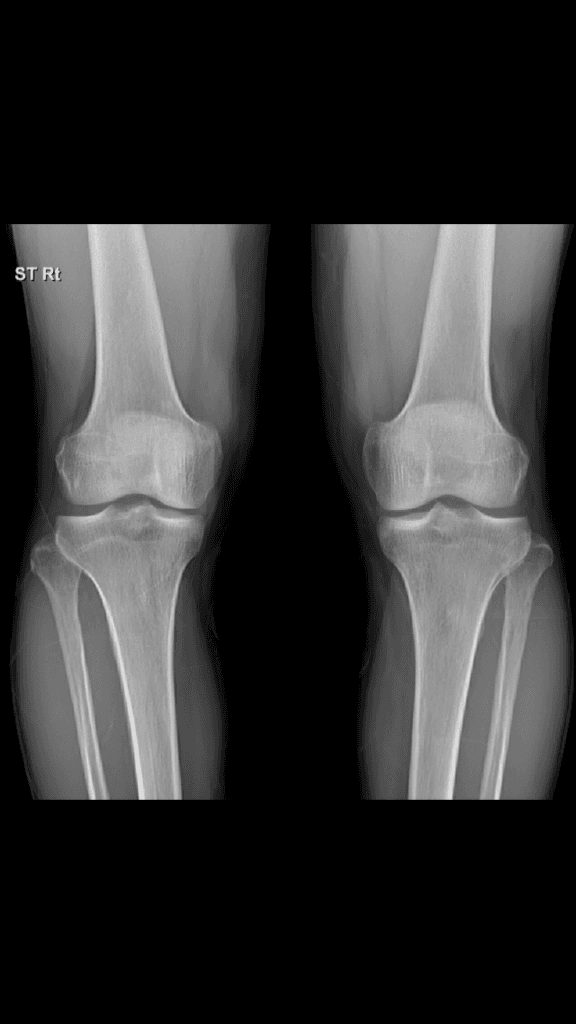

엑스레이 검사를 통해서는 연골이나 인대 등에 대한 구조물은 평가 가능하지 않습니다. 올리신 사진의 엑스레이 소견에는 특별히 문제가 있어 보이는 부분이 있어 보이지 않습니다. 정상적으로도 안쪽이 바깥쪽보다 다소 뼈 사이 공간이 좁을 수 있습니다.

올려주신 무릎 엑스레이를 보면 양쪽 무릎 관절 간격이 조금 차이가 나고 왼쪽 무릎 안쪽 관절 간격이 상대적으로 좁아진 것처럼 보입니다.

이는 일반적으로 내측 관절 연골이 닳아 발생하는 초기 퇴행성 변화일 가능성을 시사합니다.

사람마다 양쪽 무릎 간격이 약간 다를 수 있지만 통증이 있고 한쪽이 유독 좁아진 경우에는 퇴행성 변화 가능성을 고려해야 합니다!